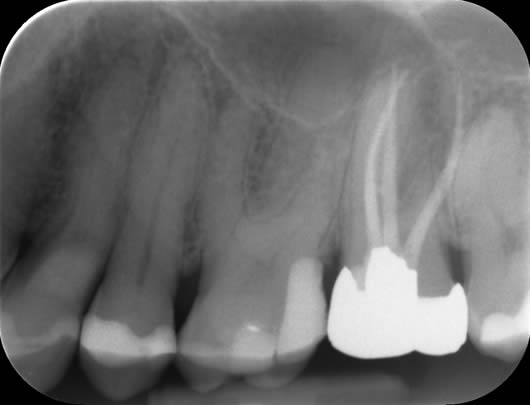

Case 3: Root canal treatment – narrow canals.

As a tooth ages, whether prematurely following trauma or long-term irritation, or in accordance with natural ageing, the root canals can become narrower due to the laying down of further dentine (tooth structure). This can make the canals difficult to locate and very challenging to negotiate to full length. As with finding the elusive MB2 canal (Case 2), we use our experience and the use of the dental microscope to conservatively remove tooth tissue in just the right areas to locate these canals. This cases shows a tooth (UL6) in which it is difficult to see the canals on the radiograph as they are very narrow. We were able to locate four canals (including the challenging MB2 canal) and prepare and fill them.

Before treatment UR6

Following root canal treatment UR6